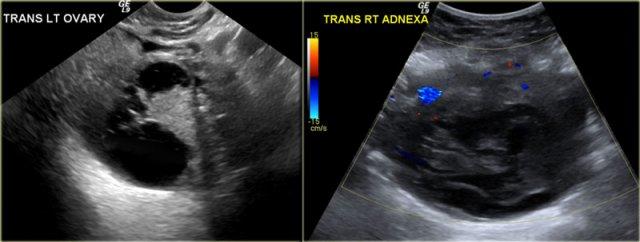

Siêu âm đường âm đạo cho thấy tổn thương dạng nang giảm âm kích thước lớn với các echo mức độ thấp lan tỏa

Lạc nội mạc tử cung dạng nang (Endometrioma)

Lạc nội mạc tử cung dạng nang (endometrioma) là loại nang hình thành khi mô nội mạc tử cung phát triển trong buồng trứng.

Bệnh ảnh hưởng đến phụ nữ trong độ tuổi sinh sản và có thể gây đau vùng chậu mạn tính liên quan đến chu kỳ kinh nguyệt.

Buồng trứng bị tổn thương ở khoảng 75% bệnh nhân mắc lạc nội mạc tử cung.

Trên siêu âm, hình ảnh endometrioma có thể đa dạng, nhưng đại đa số (khoảng 95%) bệnh nhân biểu hiện hình ảnh điển hình là nang đồng nhất, giảm âm với các echo mức độ thấp lan tỏa.

Hiếm gặp hơn, tổn thương có thể không có echo, dễ nhầm lẫn với nang buồng trứng chức năng.

Endometrioma có thể có nhiều ngăn và có các vách ngăn mỏng hoặc thậm chí dày.

Siêu âm qua đường âm đạo: endometrioma với hai ổ tăng âm ở thành, phù hợp với lắng đọng cholesterol (mũi tên)

Ở khoảng một phần ba số bệnh nhân, khi khảo sát kỹ có thể thấy các ổ tăng âm nhỏ bám vào thành nang.

Các ổ này được cho là lắng đọng cholesterol, nhưng cũng có thể là các cục máu đông nhỏ hoặc mảnh vụn.

Điều quan trọng là cần phân biệt các ổ này với các nốt thành thực sự.

Khi có sự hiện diện của các ổ này, chẩn đoán endometrioma là rất có khả năng.

Hình siêu âm qua đường âm đạo cho thấy hình ảnh endometrioma điển hình với các ổ tăng âm ở thành.

Trên siêu âm Doppler, không ghi nhận tín hiệu mạch máu trong các ổ này (không hiển thị).

Trường hợp tiếp theo là hình siêu âm qua đường âm đạo cho thấy một tổn thương dạng nang có cấu trúc tăng âm.

Chẩn đoán phân biệt rộng bao gồm: u nang buồng trứng có thành phần đặc, u quái dạng nang trưởng thành với nốt Rokitansky tăng âm, nang xuất huyết có cục máu đông và endometrioma có cục máu đông hoặc mảnh vụn.

Tiếp tục xem hình ảnh CT và MRI.

CT được chỉ định và cho thấy tổn thương tương tự, chủ yếu là dạng nang.

Khi cần chẩn đoán hình ảnh bổ sung cho các nang không xác định được trên siêu âm, nên ưu tiên thực hiện MRI.

Hình chuỗi xung T2W bên phải tương quan tốt với hình siêu âm.